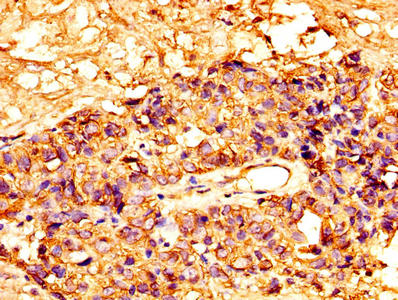

IHC image of CSB-PA10159A0Rb diluted at 1:300 and staining in paraffin-embedded human breast cancer performed on a Leica BondTM system. After dewaxing and hydration, antigen retrieval was mediated by high pressure in a citrate buffer (pH 6.0). Section was blocked with 10% normal goat serum 30min at RT. Then primary antibody (1% BSA) was incubated at 4°C overnight. The primary is detected by a biotinylated secondary antibody and visualized using an HRP conjugated SP system.